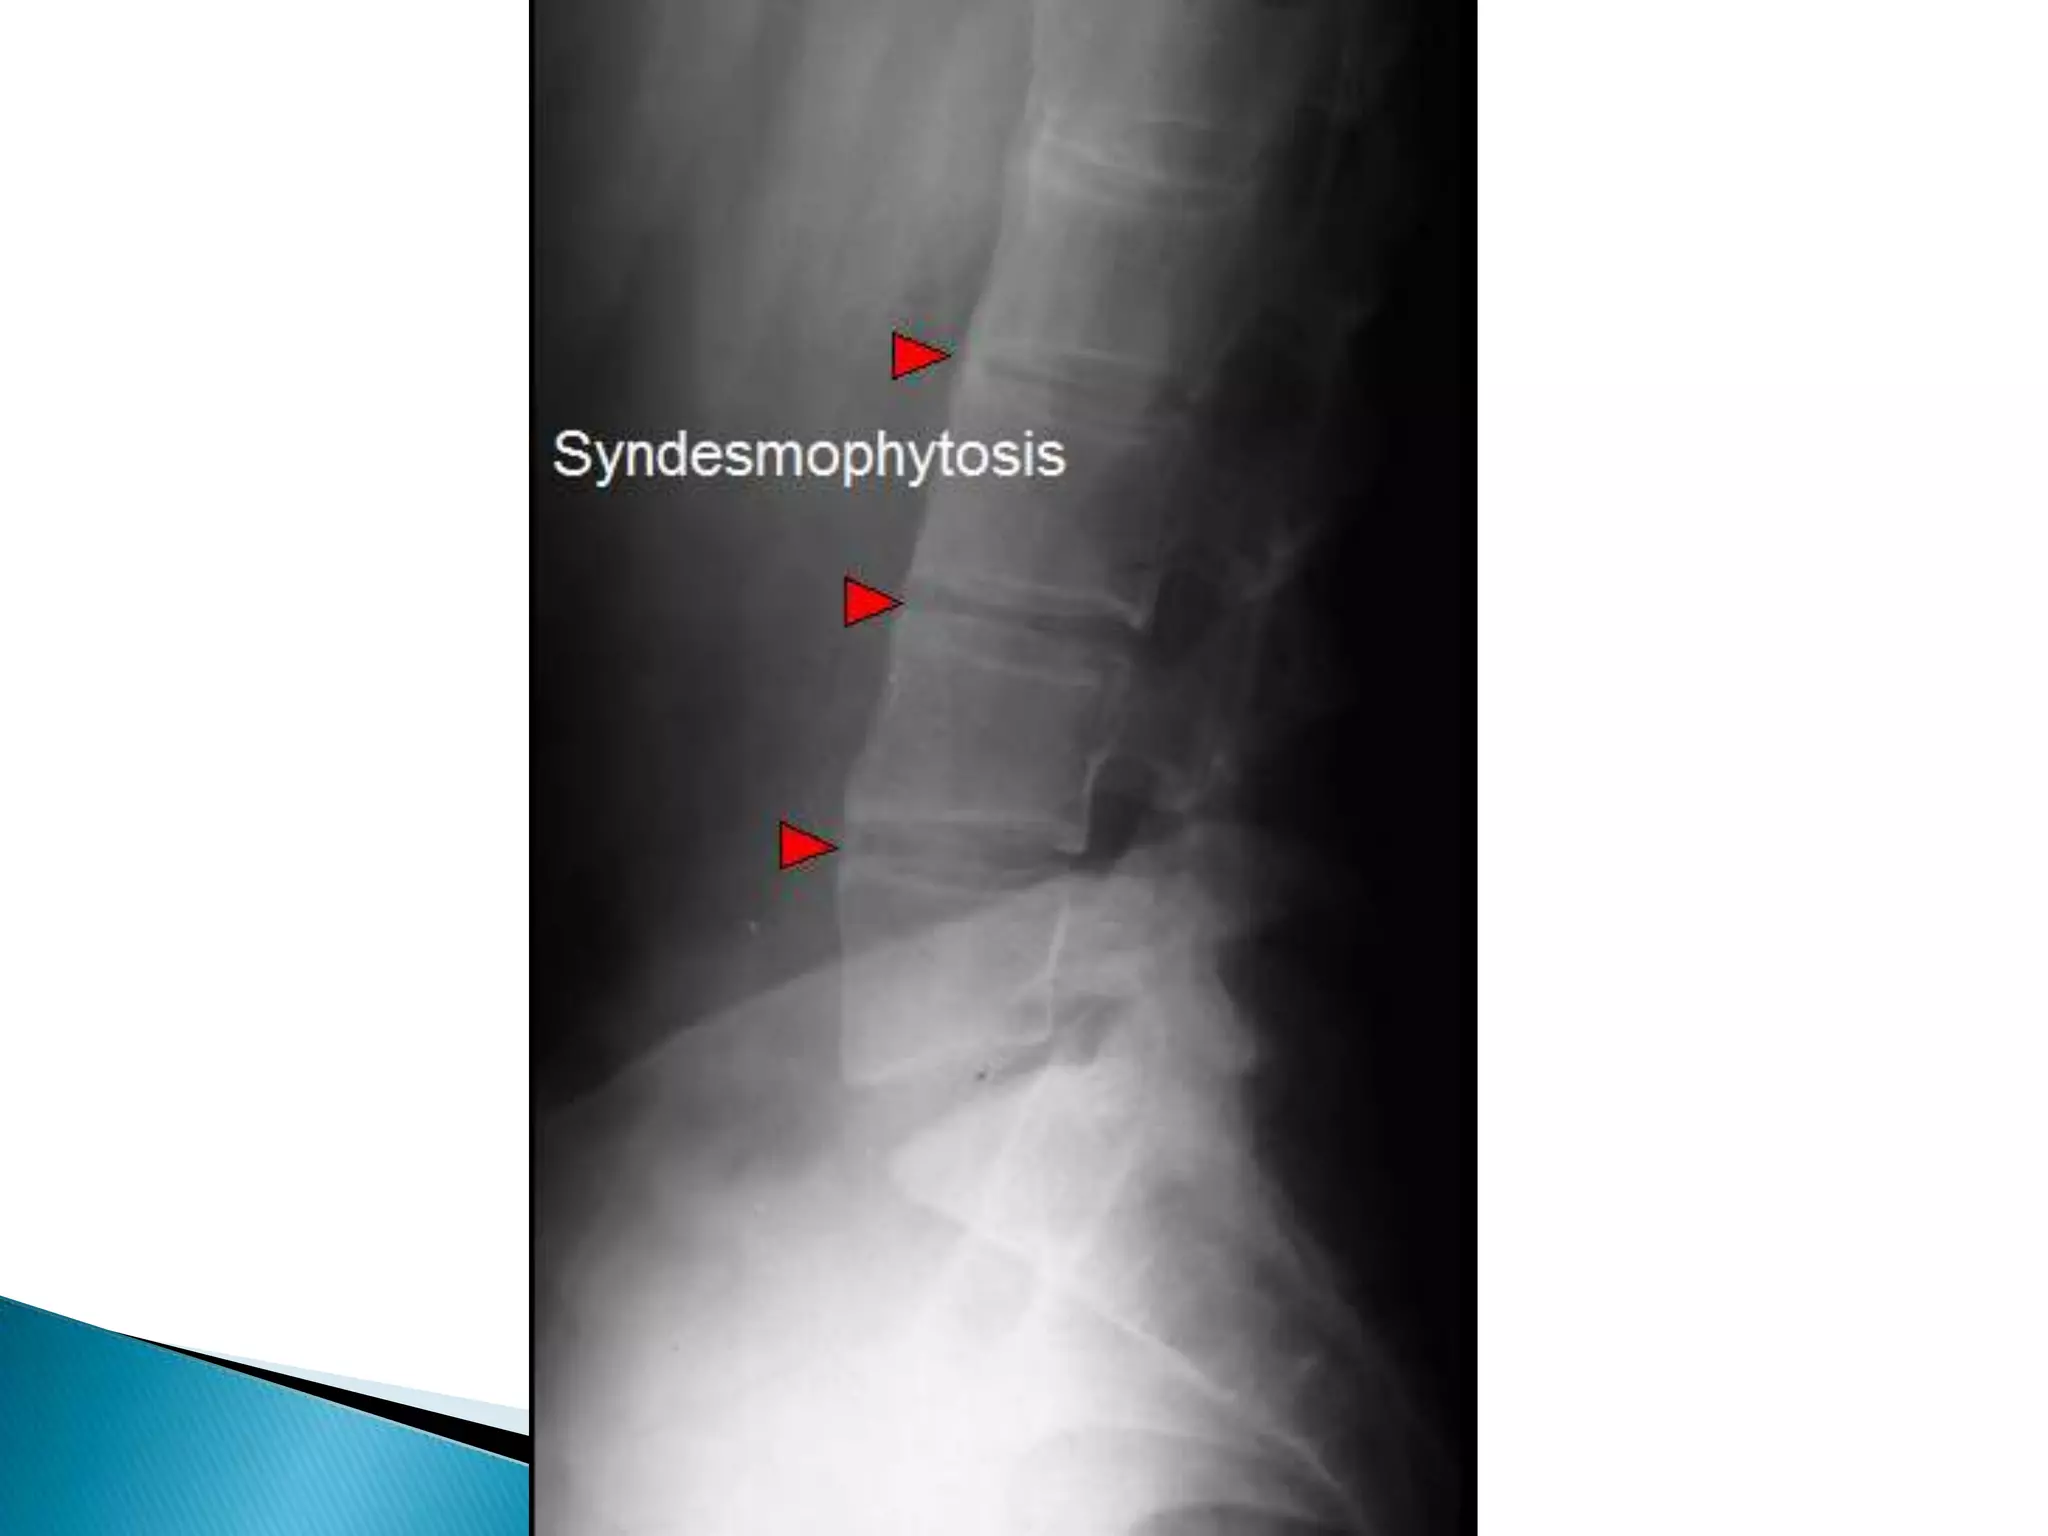

Radiological finding of ricketsThe changes are  maximal where bone growth is occur, so they best seen in the knees, wrists & anklesLoss of provisional zone of calcification.Indistinct metaphyses& metaphyses become irregular and cupped.Wide growth plate.decreased bone density.Deformities of the bones occur because of bone softening.Greenstick fractures are common

Radiological finding ofricketsThe changes are maximal where bone growth is occur, so they best seen in the knees, wrists & anklesLoss of provisional zone of calcification.Indistinct metaphyses& metaphyses become irregular and cupped.Wide growth plate.decreased bone density.Deformities of the bones occur because of bone softening.Greenstick fractures are common